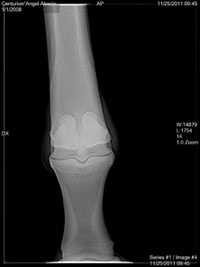

Dr. O I'm not sure is this one is from the front. If not I don't have another one. Everything else are from sides.

Angel, I do not see a medial condylar fracture in these views. I would expect such a fracture to be best seen in a ap (front to back) view rather than a lateral view like we have above. There is a rather significant piece of bone fragment, often called a joint mouse, seen in the first image above however. DrO